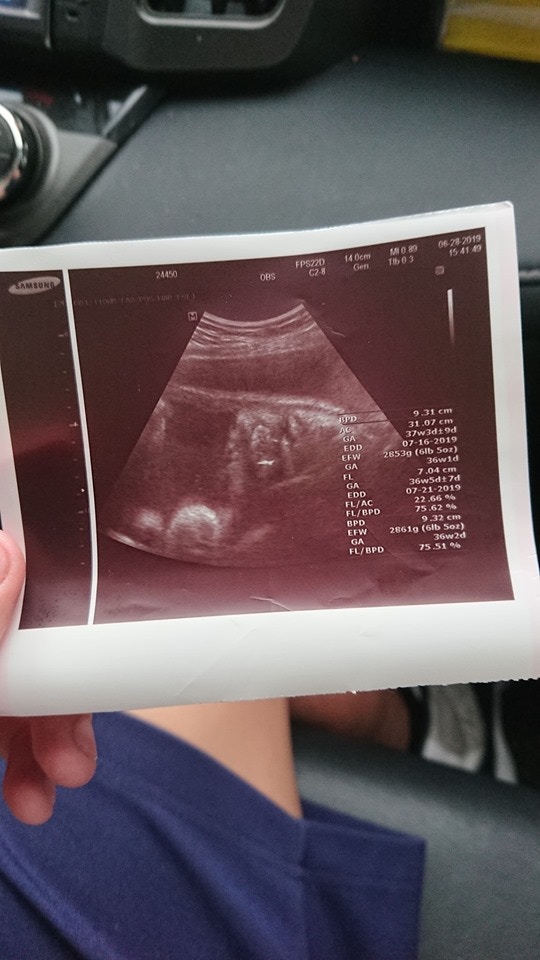

▼女方的家長非常明理,雖然很無奈,但認為事到如今責罵沒有用。兒子的女友一直不敢告訴家人,也沒有做過產檢,去醫院檢查後才發現胎兒已經37週,很快就要生了。家長們討論後,原po決定將她接回家待產。

▼為了保險起見,7月1日原po又帶兒子的女友去做產檢,結果醫生說已經開2指,立刻安排住院待產,隔天小孩順利出生。原po剛剛42歲就當上阿公,老婆才38歲就當上阿嬤,兒子只給了他們4天時間做心理準備,真的很突然。